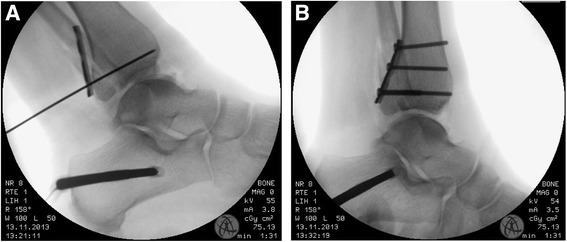

Fig. 1.

Intraoperative x-ray; a Lateral view with temporary k-wire fixation of the posterior fragment; b Lateral view after fixation with a three-hole one-third tubular plate for fixation of a posterior malleolus fracture